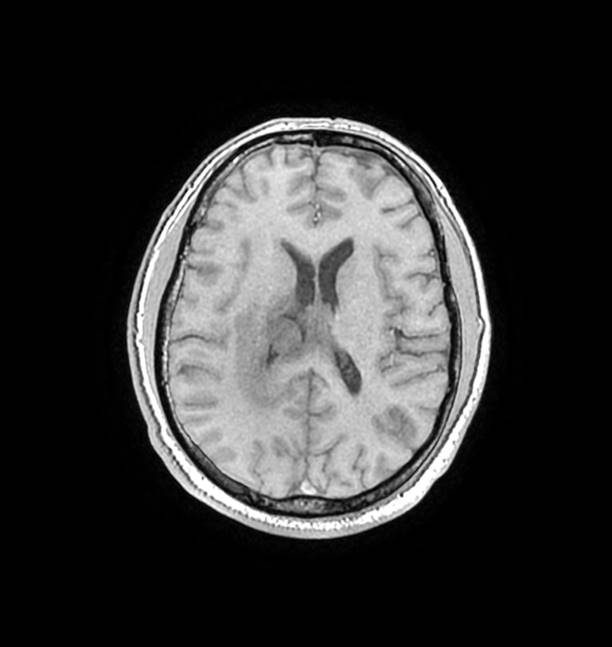

磁共振影像圖

圖1

圖2

圖3

圖4

MR診斷:右側(cè)側(cè)腦室三角區(qū)及側(cè)腦室旁占位,考慮惡性腫瘤可能,間變型腦膜瘤?轉(zhuǎn)移瘤?

MR鑒別診斷

常規(guī)MR檢查是診斷腦膜瘤的有效手段,可以明確腫瘤發(fā)生的部位、形態(tài)和數(shù)目等特征以及病變向鄰近腦實(shí)質(zhì)侵犯的程度和范圍,典型腦膜瘤呈等或(和)稍長(zhǎng)T1、等或(和)稍長(zhǎng)T2信號(hào),??娠@示完整的包膜,增強(qiáng)掃描因腫瘤內(nèi)部新生血管通透性不同呈不同程度強(qiáng)化,由于腫瘤組織的強(qiáng)化程度與腫瘤的惡性程度不完全一致,導(dǎo)致MR常規(guī)檢查在腦膜瘤分級(jí)分型方面仍存在一定的困難。擴(kuò)散加權(quán)成像( diffusion weighted imaging,DWI) 及表觀擴(kuò)散系數(shù)( apparent diffusion coefficient,ADC) 被廣泛用于腦腫瘤的分級(jí)、分子分型和腫瘤侵襲性預(yù)測(cè),并取得了良好的性能。目前,對(duì)于非典型腦膜瘤腦實(shí)質(zhì)侵犯的診斷的金標(biāo)準(zhǔn)依賴于組織病理學(xué)。